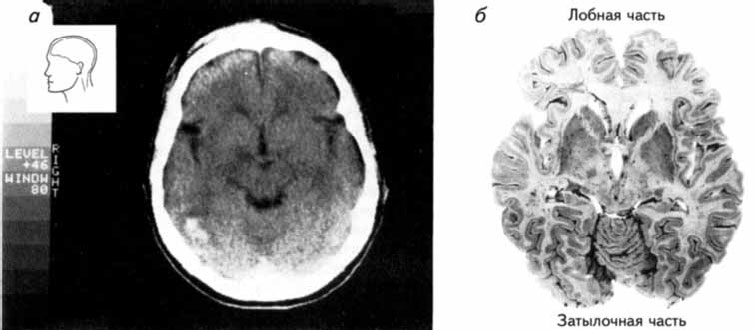

Рис. 2.14. Сканирование с помощью метода компьютерной томографии.

(а) Снимок, полученный на компьютерном томографе; (б) Фотография среза мозга на том же уровне, что и на снимке, приведенном на рисунке (а) (Carlson, 1992).

Для улучшения качества изображения перед исследованием пациенту вводят контрастное вещество. Особенно эффективна компьютерная томо графия для исследования повреждений мозга, например, вследствие инсульта (рис. 2.15), рассеянного склероза, опухолей. Кроме очевидной необходимости этого метода для хирургического исследования перед операциями он представляет значительный интерес для психофизиологов и нейрофизиологов, которые изучают когнитивные процессы и поведение людей, имеющих повреждения мозга.

Информативность томограмм увеличивается благодаря применению контрастных веществ, например, верографина (препарата, содержащего йод). Полученная информация в виде снимков может храниться на магнитных носителях, что позволяет пересылать их по каналам компьютерной связи на любые расстояния для консультации специалистов (Лалаянц, Милованова, 1991).